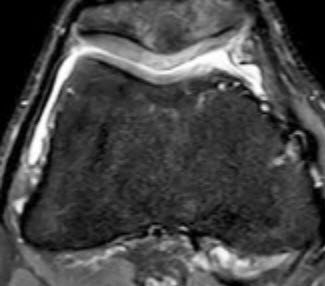

Etwa drei bis vier Wochen nach der Entnahme können die Zellen wieder eingesetzt werden. Dies geschieht in einer zweiten, dann offenen Operation, bei der die eigenen Knorpelzellen, bereits auf einer dreidimensionalen Matrix besiedelt und passgenau auf die Defektgrösse zugeschnitten, eingesetzt und mit einem sehr feinen Faden am umliegenden Knorpel befestigt werden (Abb. 4). Nach Ablauf der Regenerationszeit konnte der Patient wieder schmerzfrei den Alltag bewältigen und im späteren Verlauf auch die volle sportliche Aktivität wieder aufnehmen. Es bestanden keine Beschwerden mehr im Bereich des rechten Kniegelenks. Das Kontroll-MRI ein Jahr nach der Operation zeigte eine wiederhergestellte Knorpeloberfläche mit guter Integration des Transplantates sowohl in den umliegenden Knorpel als auch in den unterliegenden Knochen. Dabei wies das Transplantat selbst eine dem umliegenden Knorpel vergleichbare Signalgebung auf – als Zeichen der physiologischen Regeneratqualität.